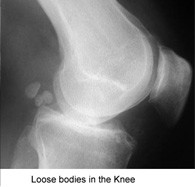

Loose bodies in the knee